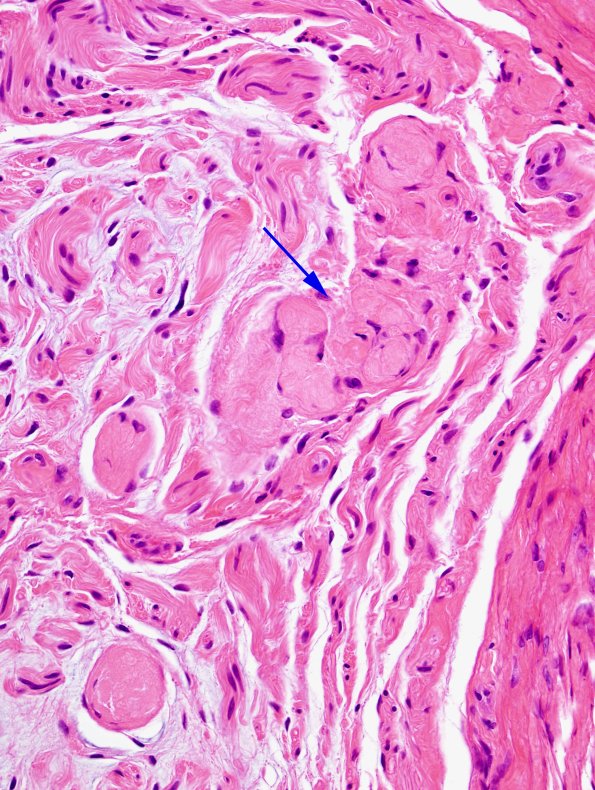

The biopsy material shows cross sections of peripheral nerve consisting of multiple fascicles with mild-to-severe loss of large and small myelinated axons. There are solid collections of collagen (arrow, 15A2) that appear to represent collagenized Renaut bodies. (H&E)